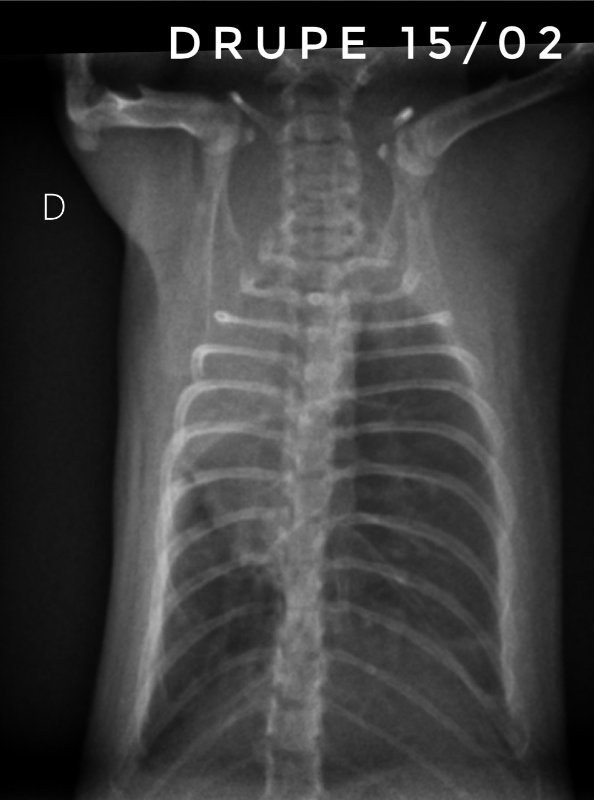

Toujours pour ceux que ça intéresse, les dernières  radios et le suivi du poids (Pyridion a commencé à perdre du poids le 04 mars, traitement changé le 08)

Screenshot_20240319_130710-01.jpeg

Screenshot_20240319_130507-01.jpeg

Screenshot_20240319_130924-01.jpeg

Screenshot_20240319_130226-01.jpeg

Il nous reste donc 3 malades : Drupe, Caryopse et Pyridion.

Drupe va vraiment mieux, poumons encore touchés mais mieux quand même (mais décidément c'est bien long).